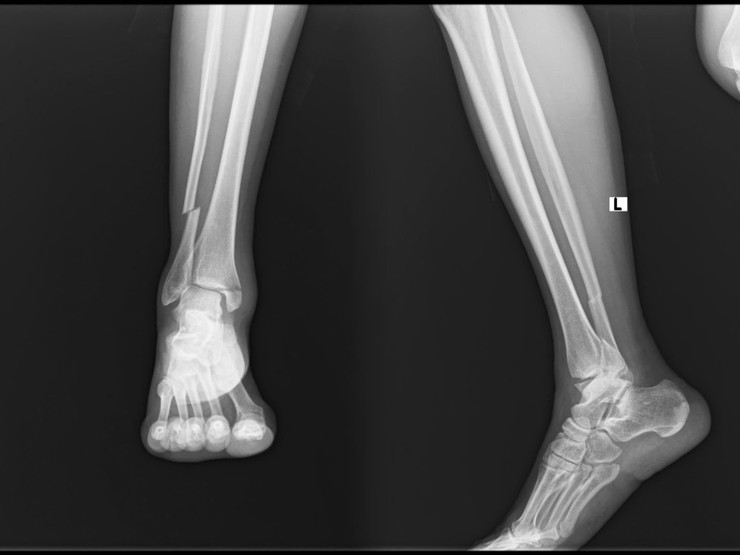

Kết quả chụp X-Quang cho thấy bệnh nhân bị gãy mắt cá trong, mắt cá ngoài, mắt cá sau, trật khớp cổ chân trái. Đây là tổn thương nặng cần được phẫu thuật cấp cứu để hạn chế biến chứng và bảo tồn chức năng chi thể

Phim chụp tai nạn bệnh nhân trước khi phẫu thuật.